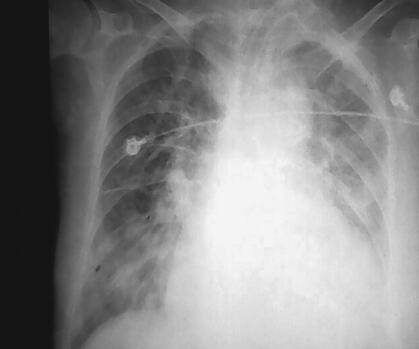

入院后立即气管插管,呼吸机辅助通气,心电、血压、氧饱和度监测,积极控制感染:头孢唑肟2.0g,每12小时1次;解痉、化痰,改善通气,改善心功能,强心、利尿、硝酸酯类扩血管治疗。经呼吸机治疗,很快意识好转,但是心功能没有明显恢复,心肌标志物检查一直在升高,TnI最高在33.8μg/L,BNP最高在17807pg/ml,呼吸机撤机困难,在呼吸机给予SIMV方式后出现急性左心衰竭,心源性休克,血压降至71/39mmHg,立即给予血管活性药物调整血压。4月10日患者体温开始升高,双肺痰鸣音增加,痰量增加,并为黄痰,胸部X线片见图2,痰涂片为革兰阳性球菌,革兰阴性球菌和革兰阳性杆菌,痰培养多次为鲍曼不动杆菌,属多重耐药型。经调整抗生素后体温逐渐好转,痰量减少,同时血中WBC在10×109/L左右,而且逐渐下降,中性粒细胞75%左右,逐渐准备撤机,胸部X线片见图3。但是患者在撤机过程中多次发作心力衰竭,出现咳粉红色泡沫样痰,同时血BNP指标逐渐上升,最高达45445.4pg/ml。4月17日将呼吸机调为机控A/C方式后逐渐好转。于4月29日行气管切开术。此时痰培养汇报均为鲍曼不动杆菌和铜绿假单胞菌,体温在38℃左右,双肺仍有大量痰鸣音、湿啰音,胸部X线片见图4,心率102次/分,血BNP 11969.6pg/ml,WBC 9.23×109/L,N 77.41%,根据药敏结果更换抗生素为头孢哌酮-舒巴坦钠3.0g,每8小时1次,联合口服米诺环素100mg,每天2次治疗,患者体温逐渐恢复,心率下降至60次/分左右,症状逐渐缓解(胸部X线片见图5)。血BNP降至6995pg/ml。但是呼吸机一直不能撤离。在抗感染的同时一直给予扩血管、利尿、改善心肌血供、改善心功能治疗,给予米力农、心钠素治疗,心力衰竭症状明显缓解,但是撤机仍然困难。终因高龄,全身状态差,出现尿路感染。尿培养、痰培养多次出现念珠菌生长(光滑念珠菌为主),尿中出现屎肠球菌生长2次。肾功能逐渐下降,血Cr最高至114μmol/L。并出现高热,白细胞升高,贫血(胸部X线片见图6)。将抗生素改为美罗培南加利奈唑胺及伏立康唑,症状逐渐改善,肾功能恢复正常,血常规正常,体温恢复正常。

图2 心力衰竭有所缓解,但右肺炎症增多